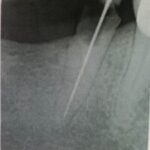

Instrument im Wurzelkanal

Perfekte Wurzelfüllung